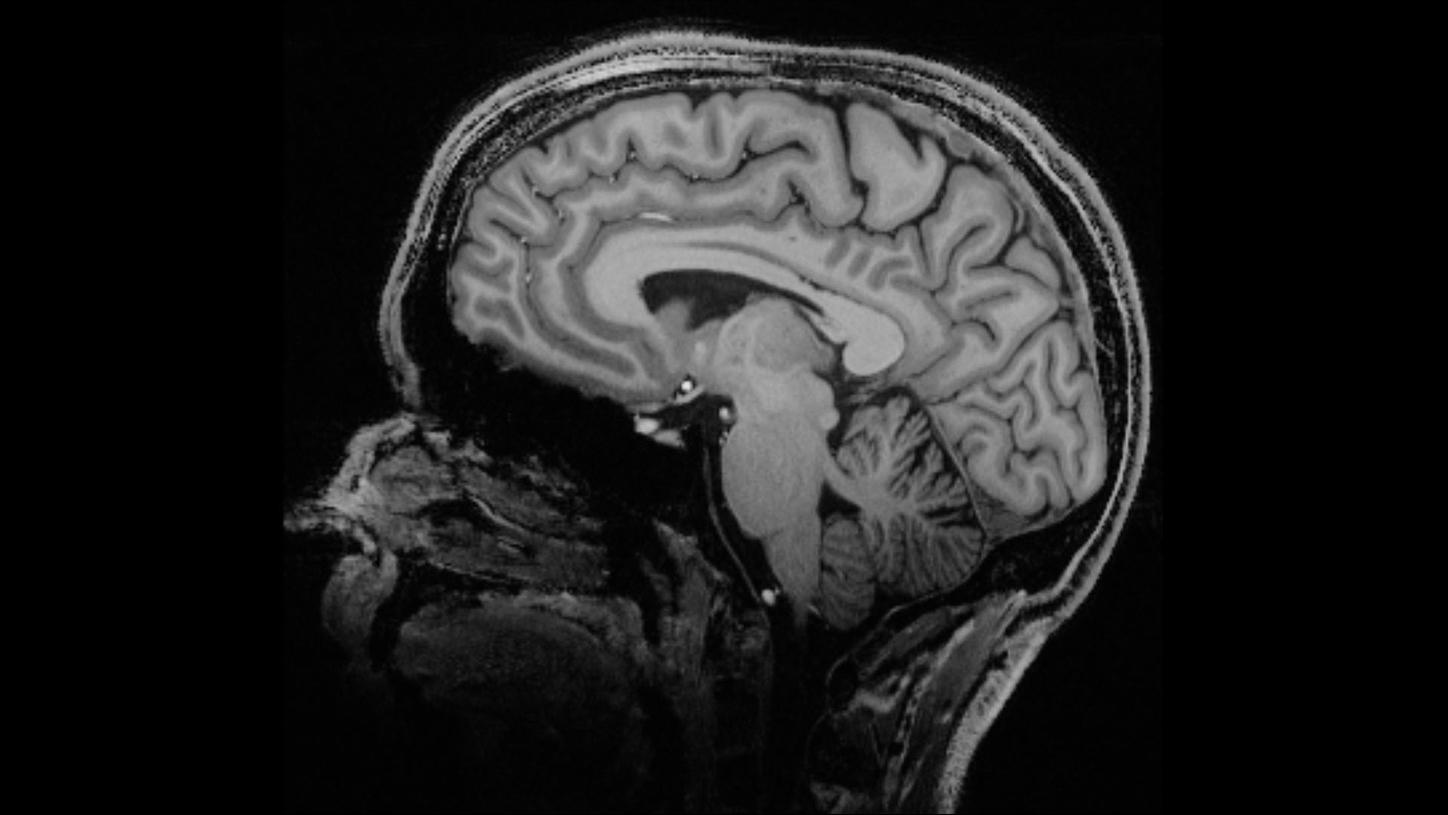

The Physics of Magnetic Resonance Imaging MRI is an imaging modality reliant on the nuclear resonance properties of tissues Every atom has a nuclear magnetic spin, an inherent property of atoms (as a consequence of it being a property of fundamental particles), which dictates its rotation about an axis through its centre These magnetic spins Recently, ultrahighfield (static magnetic field ≥ 7T) MRI has attracted increasing attention because it can provide higher signaltonoise7T MRI research in neurology initial results and future research applications The CJ Gorter Center for High Field Magnetic Resonance Imaging (MRI) at the Leiden University Medical Center was established within the Department of Radiology in late 07 The aim of the center is the development of new

The progression to 7 Tesla (7 T) magnetic resonance imaging (MRI) yields promises of substantial increase in signaltonoise (SNR) ratio This increase can be traded off to increase image spatial resolution or to decrease acquisition time However, renal 7 T MRI remains challenging due to inhomogeneity of the radiofrequency field and due toThe Magentom Terra is the first 7T MRI system cleared for clinical use in the United States The spatial resolution of 7T MRI approaches the scale of pathologies of interest in degenerative brain diseases, such as amyloid plaques and changes in cortical layers and subcortical nuclei It may reveal new information about neurodegenerative dementias, although challenges may include increased artefact production and more adverse effects We performed a systematic

See other articles in PMC that citethe published article Abstract Magnetic resonance imaging and spectroscopy (MRI/MRS) at 7T represents an exciting advance in MR technology, with intriguing possibilities to enhance image spatial, spectral, and contrast resolution A comparison between 7T MRI and arthroscopy of the shoulder has been performed by LazikPalm et al , demonstrating the feasibility of clinical protocol acquisition at 7 T with diagnostic image quality in patients with suspected tendinopathy of the rotator cuff Compared to the arthroscopic evaluation, 7T MRI led to an overestimation of 7tesla (7T) MRI displays brain tissue characteristics more crisply than the 3T MRI that is in wide use today This advanced imaging technology, approved for clinical use by the FDA in 17 but used for research at Cleveland Clinic since 14, already is having a notable impact on the diagnosis and treatment of multiple sclerosis, epilepsy, traumatic brain injury, degenerative brain